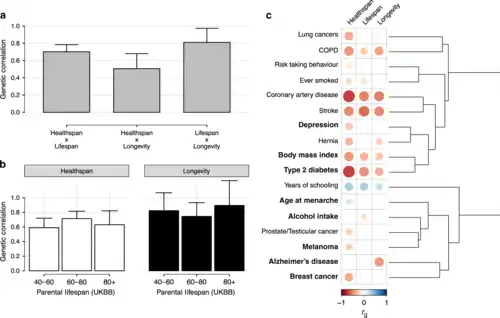

16 July: Scientists, using public biological data on 1.75 m people with known lifespans overall, identify 10 genomic loci which appear to intrinsically influence healthspan, lifespan, and longevity and identify haem metabolism as a promising candidate for further research within the field.[62]